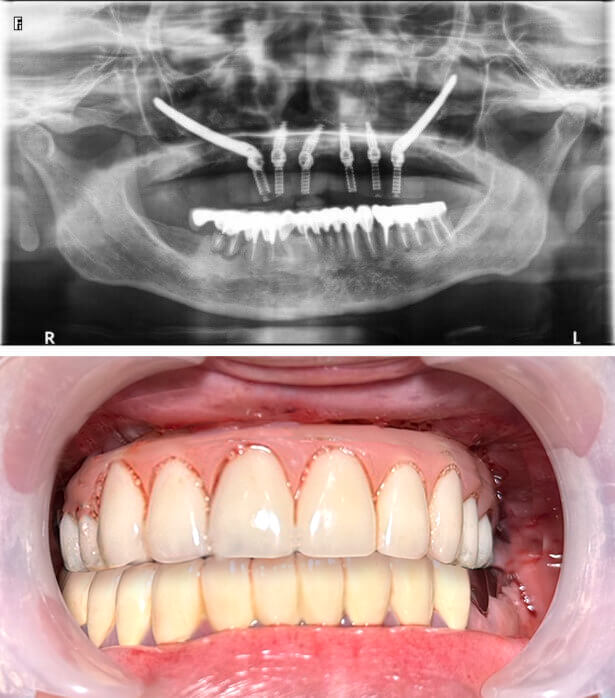

Zygomatic implant 顴骨植體治療以更長更強壯的植體,跨過萎縮骨質區植入顴骨,給予假牙穩定支撐力。如此一來,儘管患者骨質條件不佳,也能接受 All-on-4 全口重建治療。

Zygomatic implant 顴骨植體,以顴骨固定植體,是高難度全口重建手術。

顴骨植體 All-on-4:

植體固定在骨質密度更高的顴骨。

● 植體數量:6 根 (4根植體+2根顴骨植體)

● 假牙類型:上顎、整座固定假牙